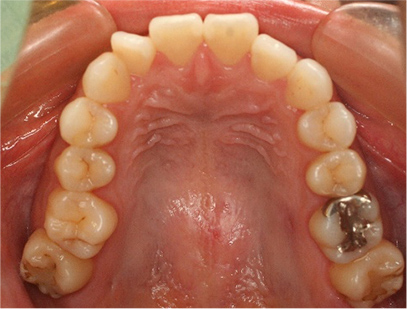

• 上側

• 下側